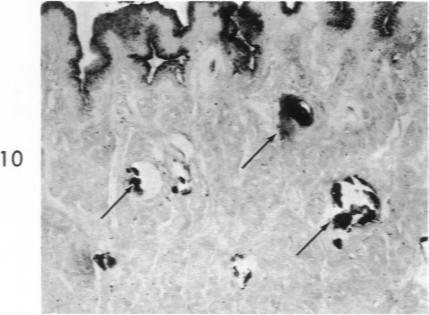

Histochemical and morphologic changes in gastric mucosa of dogs on ulcerogenic regimen.

Am J Pathol. 1969 Jul;56(1):129-51.